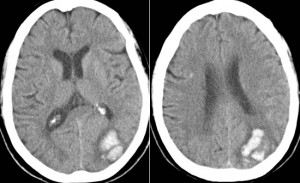

Tomografía computarizada cerebral.

Hemorragia cerebral.